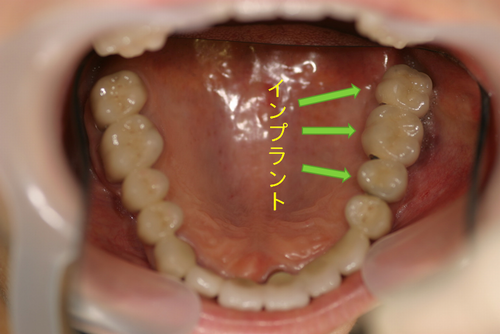

この患者様は、右上の奥歯の歯茎から出血してくるとのことで来院されました。歯周組織検査とレントゲンで診断を行った結果、重度の歯槽膿漏が認められ、保存不可能の為、抜歯になると伝えたところ、入れ歯は絶対に嫌だと言われたので、インプラント治療となりました。CT撮影を行ったところ、上顎洞底までの距離が3ミリ程度しかなかったのですが、骨が固く、フィクスチャーの一次固定が良好だったので、開窓法による上顎洞底挙上術とフィクスチャーの埋入を同時に行いました。約10カ月後に二次手術を行い、上部構造をセットしました。また、右下の臼歯部のブリッジにも大きな二次カリエスが認められ、7番の遠心根が抜歯になり、6番、7番にインプラント治療をしました。